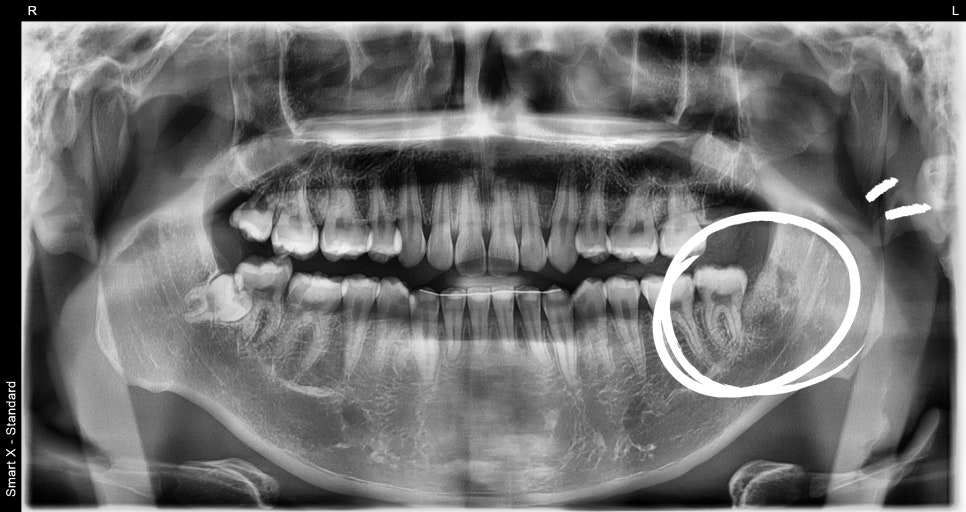

내원당시 초진 엑스레이 사진

파노라마 및 소형 엑스레이 촬영 결과,

하악 좌측 제3대구치 아래 6mm 이상의

방사선 투과성 병소(검게 보이는 낭종 조직)가 확인되었고,

치아 낭종으로 의심되었습니다.

해당 치아는 발치 없이 살릴 수 있는 상태였기 때문에,

낭종 제거 수술과 함께 매복 사랑니 발치를 계획하였습니다.